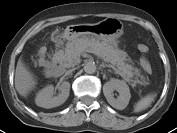

问题 男,30岁,上腹部剧痛,恶心呕吐,压痛反跳痛,血细胞计数升高,血和尿淀粉酶升高,影像表现如图,最可能的诊断是什么 ( )

选项 A、急性胰腺炎 B、慢性胰腺炎 C、胃溃疡穿孔 D、胰腺癌 E、急性肠梗阻

答案 A